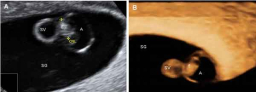

Ecografía: ¡Embrión de 5 semanas!

Al comienzo de la semana 5 de embarazo el embrión mide aproximadamente 2 milímetros. En este tiempo, el tamaño embrionario se estima midiendo su longitud total. Un poco más adelante, cuando el embrión ya empieza a tener forma y distinguimos las extremidades, medimos la longitud cráneo...